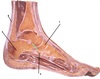

Weakness in plantar flexion of foot

reduced ankle reflex

How well did you know this?

1

Not at all

2

3

4

5